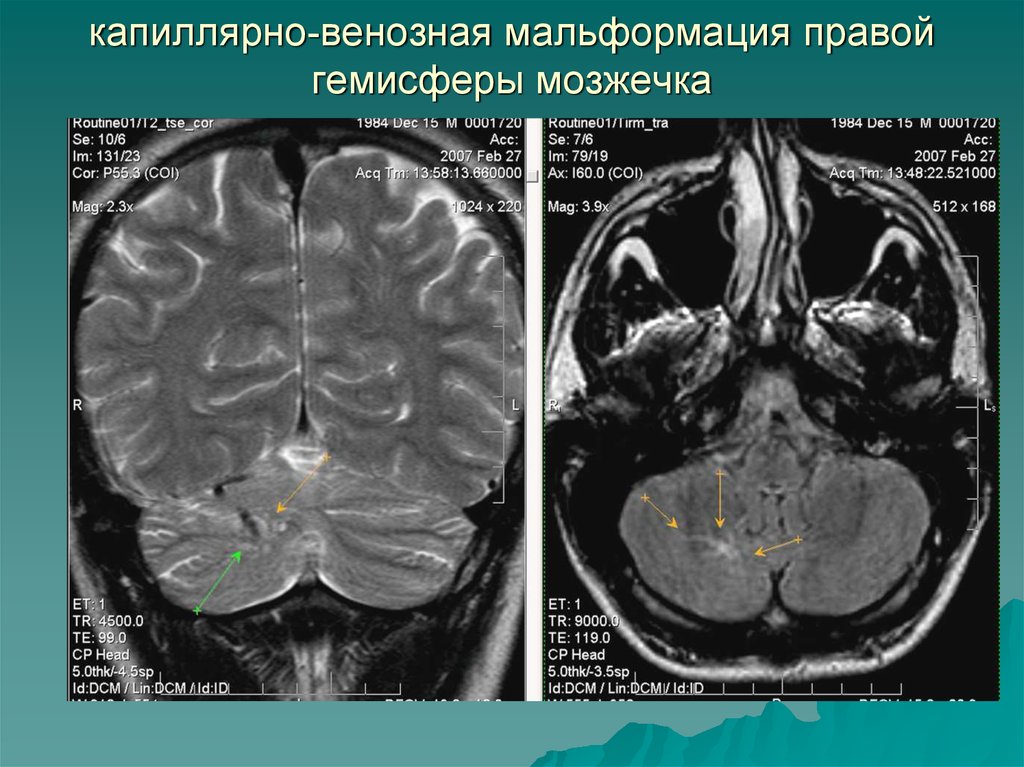

Мр картина венозной ангиомы левой гемисферы мозжечка - 96 фото